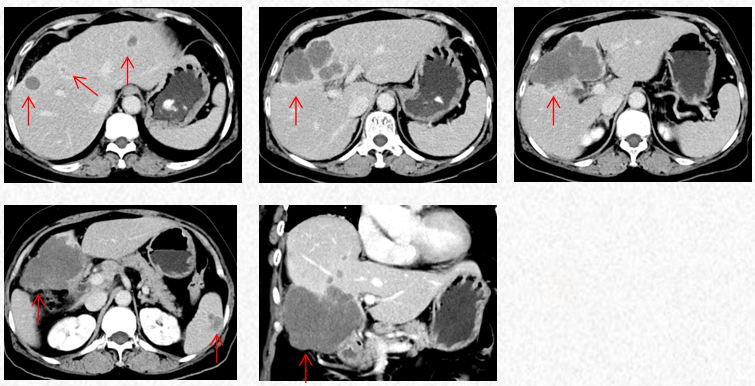

2023-3-19复查胸腹CT图片,最佳疗效评估为PR。

2023-3-19胸腹CT:肝肿物最大横截面积91*60mm,脾脏转移瘤(19*12mm)

2023-5-22胸腹CT:肝肿物最大横截面积86*58mm,脾脏转移瘤(19*12mm)

2023-7-15胸腹CT:肝肿物最大横截面积86*58mm,脾脏转移瘤(19*12mm)